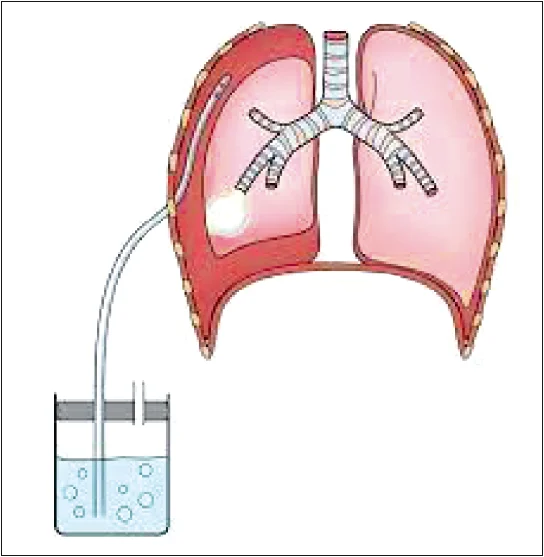

Лікувальні дії: припинення операції, негайна десуфляція, проведення рентгенографії легень, дренування плевральної порожнини (рис. 24, 25).

Рис. 24. Правобічний пневмоторакс на рентгенограмі грудної клітки: стрілками вказана вісцеральна плевра, що покриває праву легеню

Рис. 25. Дренування плевральної порожнини за Бюлау при правобічному пневмотораксі